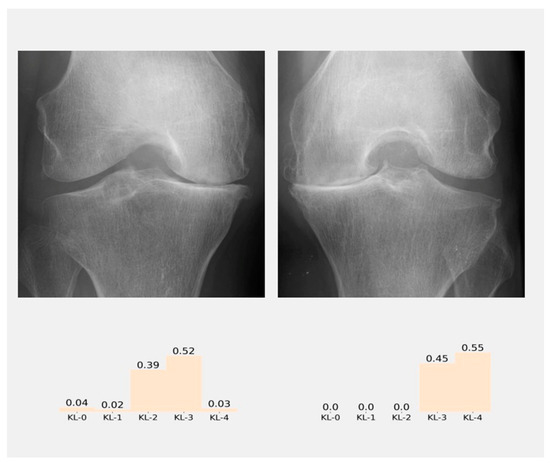

3.1. Classification of KL Degrees

3.3. Classification and User Interface